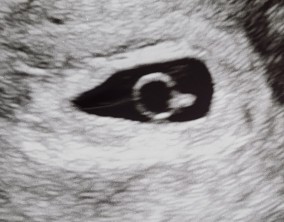

불안한 주수 끝에 찾아온 감격의 순간

대기시간이 길지 않은 점이 정말 좋았고, 무엇보다도 이유정 원장님과 선생님들 모든 직원분들이 친절해서 늘 편안한 상태로 진료를 받을 수 있었습니다. 전체적으로 쾌적하고 …